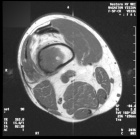

L.L. - 57 year old AA male with a greater than three month history of pain in the back of his right knee

Zoom image: Radiological image Radiological image.